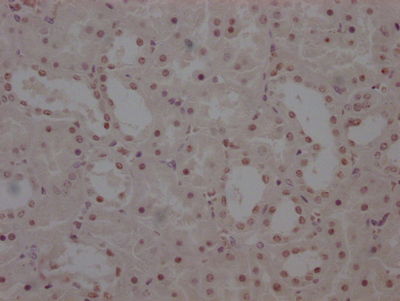

Immunohistochemistry of paraffin-embedded human testis tissue using CSB-PA525314HA01HU at dilution of 1:100